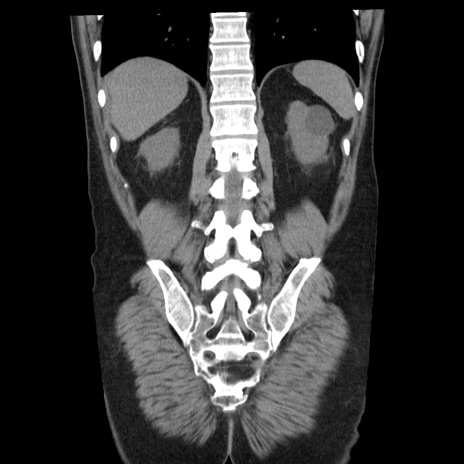

横断像

【症例】40歳代男性

【現病歴】2日前から胃痛あり。徐々に周期的な激痛に変化した。本日になっても激痛があるため受診。

【身体所見】意識清明、BT 38-39℃台あり、腹部:膨満、やや硬、右下腹部に圧痛あり。

【データ】WBC 8500、CRP 23.26